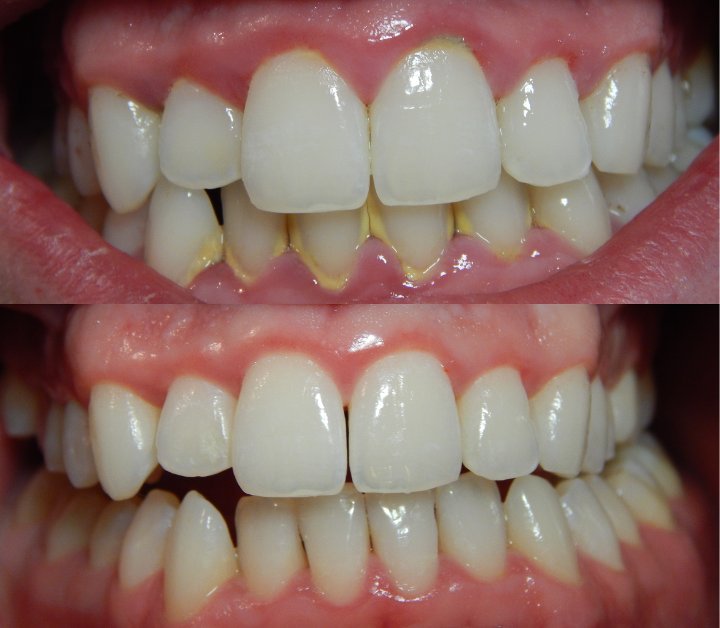

ΘΕΡΑΠΕΙΑ: Καθαρισμός από τον οδοντίατρο και εφαρμογή σωστής και επιμελούς στοματικής υγιεινής με χρήση οδοντόβουρτσας και οδοντικού νήματος. Από τις πρώτες κιόλας μέρες τα ούλα θα επανέλθουν στη φυσιολογική τους κατάσταση